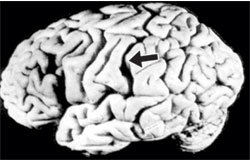

알베르트 아인슈타인의 뇌 사진. 미국의 병리학자 토머스 하비가 촬영한 것으로 화살표 부분은 ‘실비우스 주름’. 이 주름은 일반인의 뇌에서보다 더 크다.    -동아일보 자료사진

논문에 따르면 아인슈타인의 뇌에서 위쪽 가운데 부분과 양쪽 옆부분을 가르는 커다란 주름인 ‘실비우스 주름’이 보통 남성들보다 커서 머리꼭대기의 돌출부인 ‘두정엽’이 상대적으로 크다. 위틀슨 교수는 논문에서 “실비우스 주름이 있는 지역이 수학적 사고와 공간 추론을 다루는 곳”이라고 주장했다.